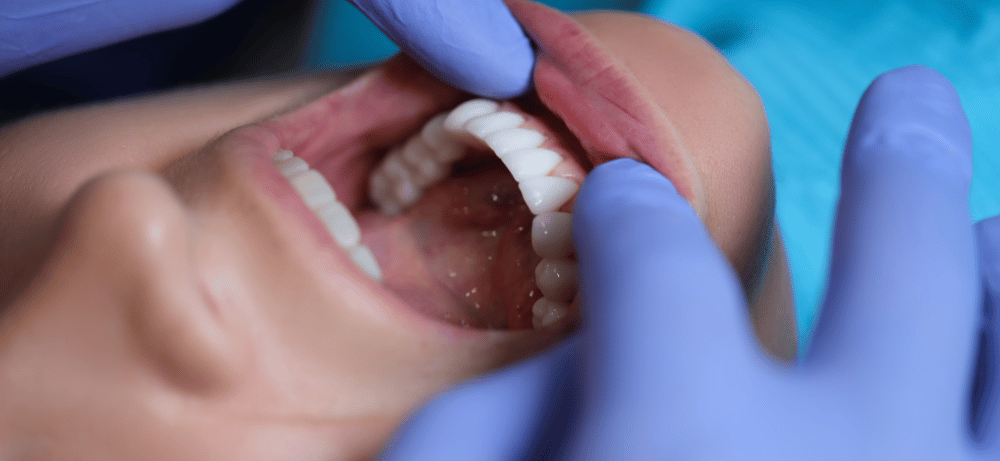

Drömmen om att ha ett strålande Hollywood smile har blivit en allt vanligare trend bland människor världen över. Det är inte längre bara något för kändisar och filmstjärnor – tack vare avancerad tandvårdsteknik är det möjligt för nästan vem som helst att uppnå perfekta tänder. Hollywood Smile har blivit en eftertraktad behandling inom estetisk tandvård och kombinerar olika behandlingar, såsom tandblekning, skalfasader, kronor och ibland tandreglering.

Hollywood smile refererar till flera estetiska behandlingar som ger ett perfekt, glänsande vitt leende, liknande de som ofta ses hos kändisar och filmstjärnor i Hollywood. Behandlingen kan inkludera olika behandlingar som tandblekning, skalfasader, tandkronor, tandreglering eller andra kosmetiska behandlingar. Målet med ett Hollywoodsmile är att skapa ett symmetriskt, välbalanserat leende där tänderna är raka, enhetligt formade och strålande vita.

För att få ett Hollywood smile kan det krävas olika tandvårdsbehandlingar, beroende på individuella behov och önskemål.